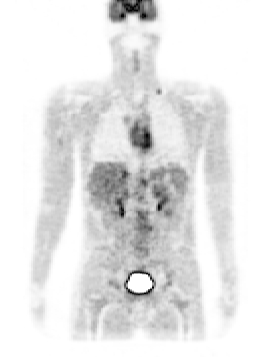

Figure 2. left: coronal slice through the Zubal phantom with inserted lesions (red points). Middle: simulated PET image corresponding to the Zubal model. Right: superimposed label model and PET simulated data.